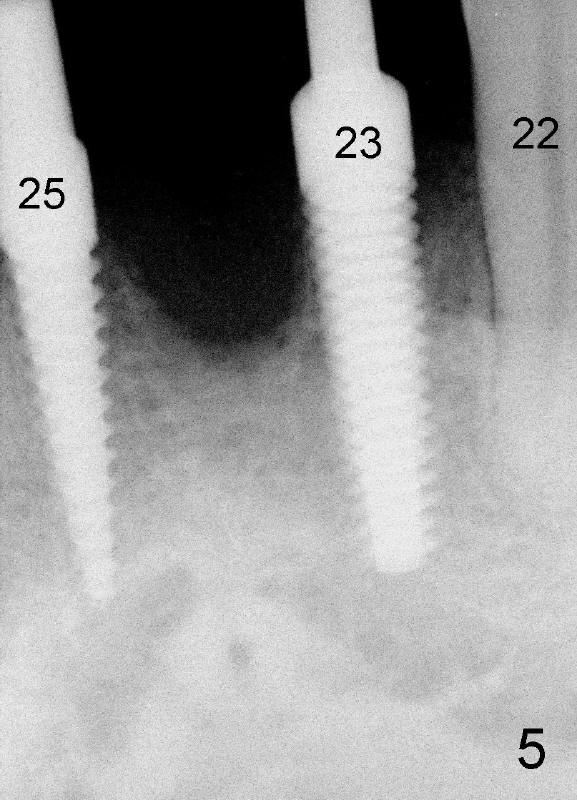

Dear Drs. Dunson and Borgner: Thank you for giving me invaluable advice, which I will use for future cases. In fact the teeth #23 and 25 were extracted last Thursday. The mesiodistal width of both roots is 3.5 mm, while the buccolingual 5 mm. It is presumed that a 4 mm implant should not perforate the buccal plate. On the other hand, the relatively large implant should fill most of the socket. Upon implant placement, the buccal plate does not feel to bulge or perforation, particularly in apical aspect, by tactile sensation. There is separation between the root of the tooth #22 and the pilot drill (1.5 mm) at the site of #23 whereas the space is limited between the pilot drill (2 mm) at the site of #25 and the root of the tooth #26. As Fig.4 and 5 indicate, a 4x17 mm one-piece implant is placed at the site of #23 and 3.5x17 mm at #25. A temporary bridge is fabricated between #23 and 25 and splinted to #22 and 27 (Fig.6). Since the abutment of the 4x17 mm one-piece implant is not tall, parallelism is not an issue after initial prep. The tooth #21 is missing. Do we still have to splint between #20 and #29 in one piece lingually?